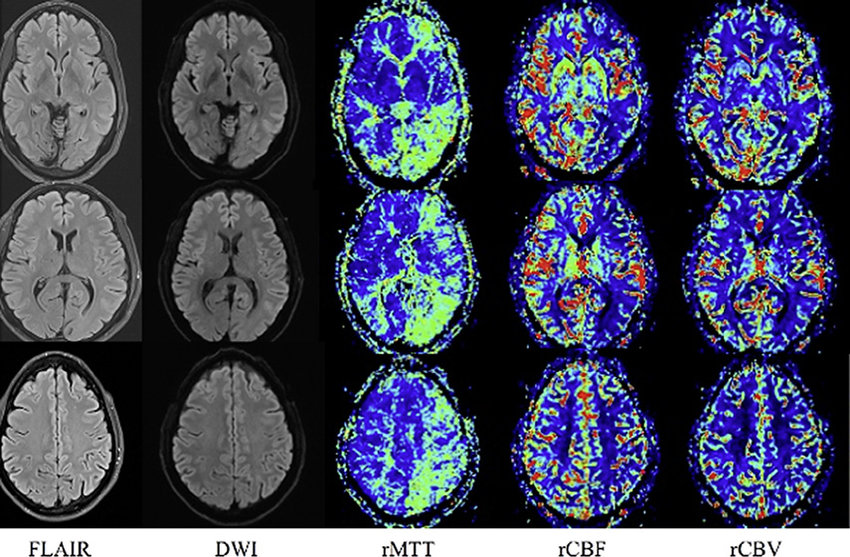

Manuscript in Preparation Perfusion software overview

Design and Implementation of a Software for Measurement of Brain Perfusion Using an Optimized Model

The NIAG perfusion software is developed for the quantitative analysis of brain perfusion MRI. It supports standard medical image formats, provides preprocessing tools such as motion correction, denoising, segmentation, and slice-time correction, and computes key DSC perfusion parameters (CBF, CBV, MTT, AUC). It also offers advanced visualization features like mirror-mode maps and customizable ROI definition for detailed regional assessment of cerebral hemodynamics. The software is intended for real clinical use in the most reputable hospitals in Iran, under the supervision of Tehran University of Medical Sciences.

My current contributions have focused on enhancing the software’s analytical pipeline, including the refinement of brain segmentation methods for complex tumor cases, improvements in preprocessing routines, and extension of manual ROI handling and visualization modules. I have also increased the quality and resolution of perfusion MRI images while ensuring precise metric calculations, and carried out the implementation and debugging of perfusion parameter calculations.